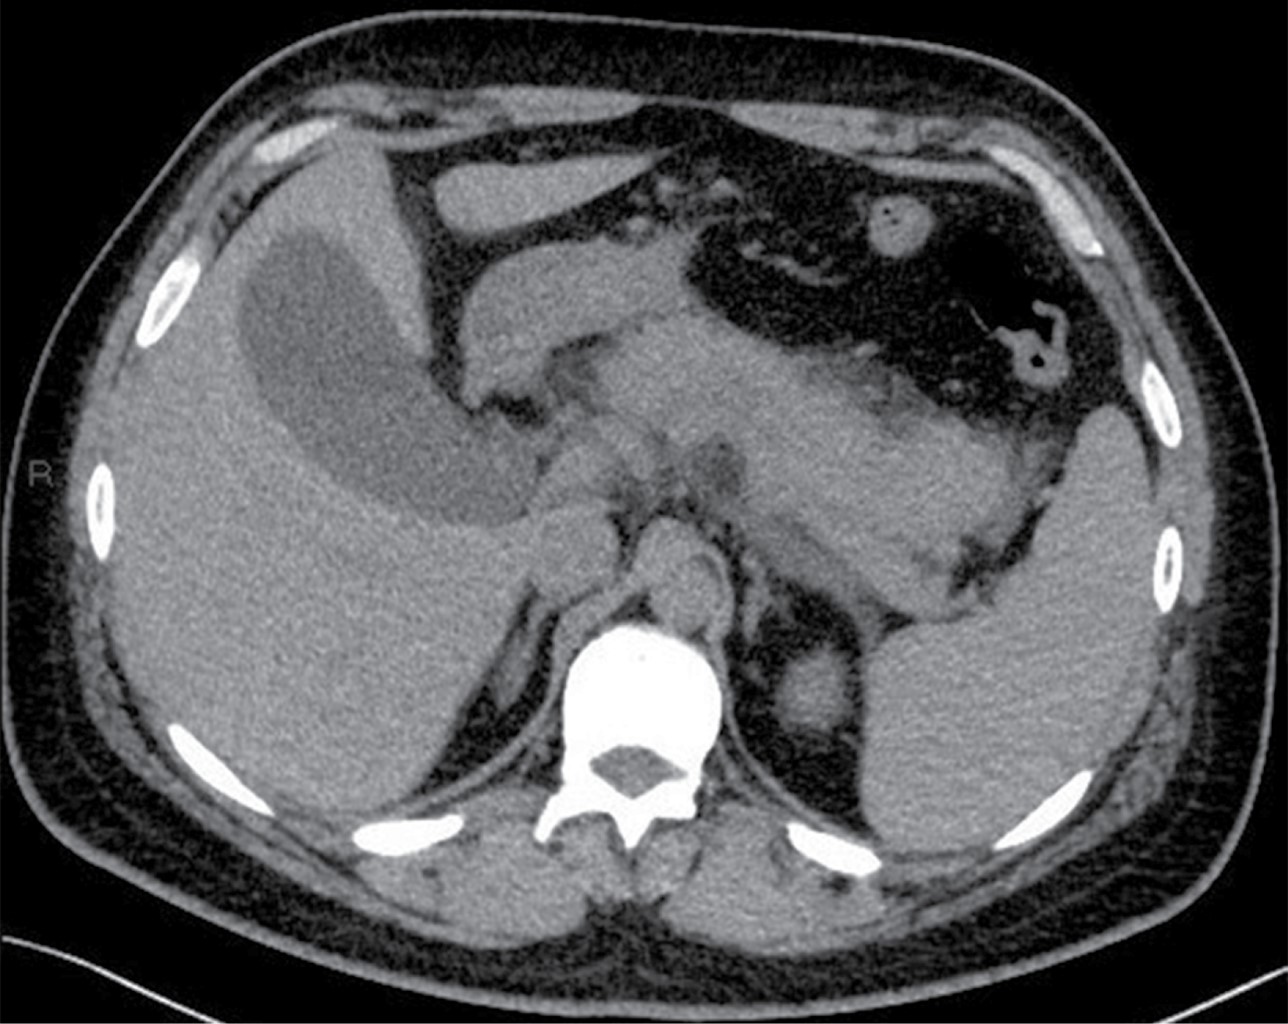

Masculino de 32 años de edad, sin antecedentes personales patológicos de importancia, acude al servicio de urgencias por presentar dolor abdominal transfictivo a nivel de epigastrio, acompañado de vómito de contenido alimenticio en dos ocasiones. Se solicitó estudio de tomografía abdominal por médico tratante, la cual se realizó con modalidad de energía dual, y definió múltiples imágenes redondeadas en vesícula biliar en relación a litiasis (Figura 1) así como aumento del volumen pancreático y estriación de la grasa adyacente compatible con pancreatitis Balthazar D (Figura 2).

La apariencia de los litos vesiculares en tomografía computarizada puede variar, los calcificados pueden distinguirse fácilmente, pero los no calcificados son isointensos en tomografías convencionales tomadas a 120 kVp.3 La litiasis biliar isointensa y la bilis son difíciles de distinguir debido a su densidad similar;7 sin embargo, pueden diferenciarse utilizando técnicas de energía dual, distinguiendo y segmentando litos isointensos de la bilis, incluso con litos menores de 9 mm.6 El principio de la tomografía de energía dual se basa en la atenuación de diversos materiales expresados en unidades Hounsfield a partir de la densidad y principalmente de su número atómico efectivo cuando son expuestos a diferentes niveles de energía del haz de rayos X, uno de alta energía que va de 140 a 150 kVp, y uno de baja energía que va de 80 a 100 kVp.3,5,7